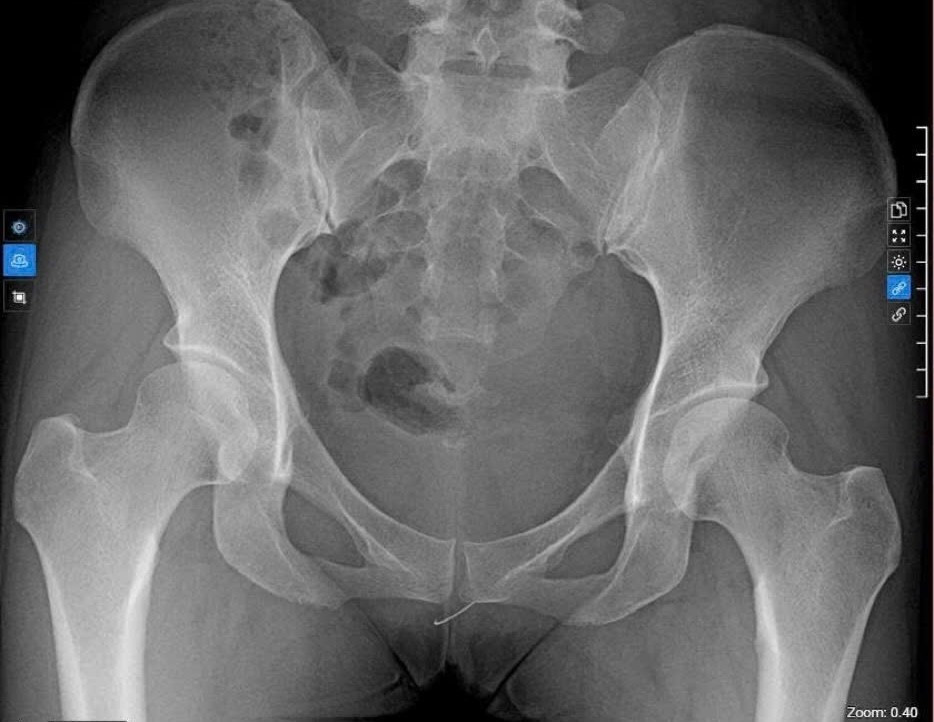

Qua chụp X-quang khung chậu và siêu âm đầu dò âm đạo, các bác sĩ phát hiện một dị vật kim loại nằm tại vùng tầng sinh môn. Sau hội chẩn liên khoa, ê-kíp đã tiến hành can thiệp, lấy ra một đoạn kim khâu nằm ở vị trí hướng 7 giờ tầng sinh môn.